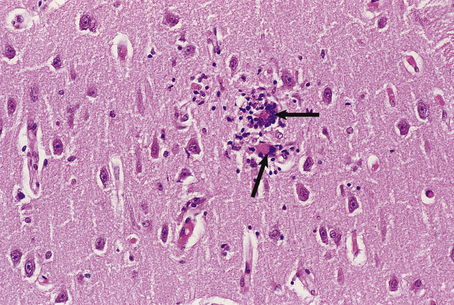

Creutzfeldt–Jakob disease

Creutzfeldt–Jakob disease (CJD) usually presents in adult life as a rapidly progressive dementia often accompanied by myoclonus, visual abnormalities and ataxia. It occurs as a sporadic disorder in 1–2 in 1 000 000 per year worldwide; familial and iatrogenic (see below) forms occur more rarely. No specific treatment is available and the disease is uniformly fatal.

The brain from affected individuals often shows widespread cerebral cortical atrophy. Microscopy of the cortex shows a loss of neurones and a reactive proliferation of astrocytes. Numerous small vacuoles are present within neuronal and astrocytic processes, hence the term spongiform encephalopathy (Fig. 26.17). No inflammatory reaction occurs in this group of disorders.

image

Fig. 26.17 Creutzfeldt–Jakob disease. The cerebral cortex shows a characteristic spongiform vacuolation (arrows) accompanied by neuronal loss and reactive astrocytosis.